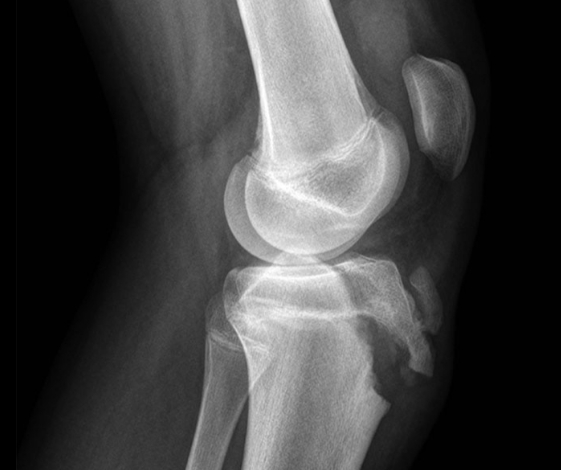

Коленный сустав имеет сложное строение. Здесь располагаются связки, сухожилия, мышечные элементы, хрящи, мениски, а также суставная жидкость в отдельной полости. Поэтому подобное исследование при помощи МРТ относят к одним из самых сложных. Ведь для постановки правильного диагноза потребуется изучить состояние каждого анатомического элемента колена. При этом потребуется учесть возраст пациента, так как он напрямую влияет на состояние сустава.